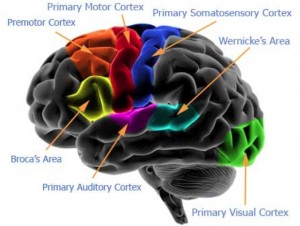

L ‘attività del cervello sano è essenziale per una salute ottimale. Il cervello è estremamente sensibile a danni dei radicali…

Caratteristiche non comuni del cervello di Einstein potrebbero spiegare le sue notevoli capacità cognitive